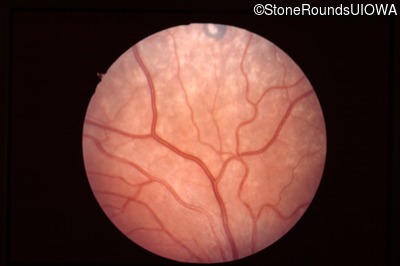

Visit at age: 7 years

Fundus Photography - Left - 20/40 -2

Exemplar